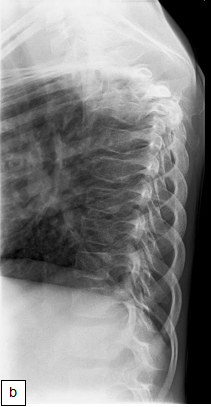

Chest X-ray (CXR): TB enlarged perihilar lymph nodes are better visualised on a lateral CXR than a PA view, therefore, it is important to obtain both PA and lateral films when evaluating a child with suspected TB.